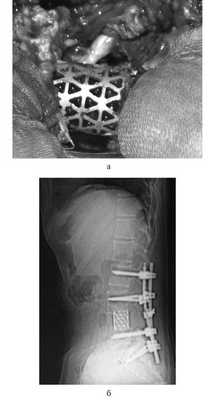

Для замещения удаленных позвонков у 8 (28%) больных применен сетчатый титановый протез «MASH» (рис. 1), который использовался нами с 2006 по 2010 г. Телескопическая система эндопротезирования, которая использовалась с 2010 по 2016 г., применена у 21 (72%) пациента (рис. 2). Спондилодез при помощи пластин выполнен у 19 (65,5%) больных, комбинированная стабилизация (титановые винты и пластины) — у 10 (34,5%) пациентов.

Рис. 1. Вертебрэктомия позвонка LIV с замещением дефекта сетчатым эндопротезом тела позвонка системой «MASH» и транспедикулярной фиксацией. а — интраоперационная фотография; б — послеоперационная рентгенограмма поясничного отдела позвоночника.